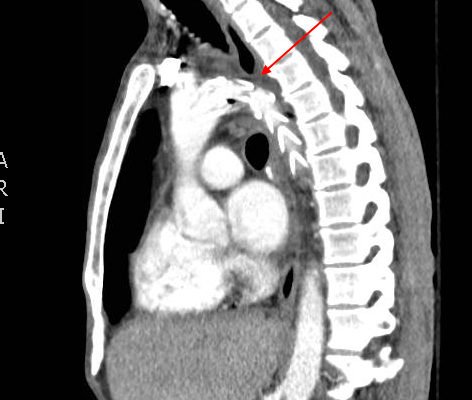

Odontoid Fracture: Computed Tomography

DOI: https://doi.org/10.21980/J8NP4WComputed Tomography (CT) of the cervical spine showed a stable, acute, non-displaced fracture of the odontoid process extending into the body of C2, consistent with a Type III Odontoid Fracture. He was evaluated by orthopedic spine service who recommended conservative, non-operative management.